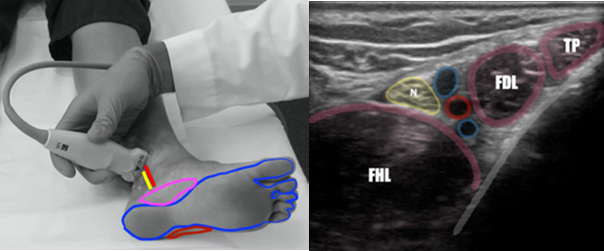

The posterior tibial nerve provides sensory innervation to the majority of the plantar foot, sparing the most medial and lateral aspects which are innervated by the saphenous and sural nerves, respectively. (Figure 1) The posterior tibial nerve is easiest identified just posterior to the medial malleolus in close proximity to the posterior tibial artery (Figure 1). At this location, both the posterior tibial artery and nerve lie between the flexor hallucis longus and flexor digitorum longus tendons as depicted by ultrasound imaging. (Figure 1)

Use of POCUS_Figure 1 r-l.pngFigure 1. Identification of the Posterior Tibial Nerve in the Distal Ankle. Left: Position of tibial nerve and artery (red/yellow lines) in location of potential blockade and nerve distribution of posterior tibial block (blue), with saphenous nerve distribution (pink) and sural nerve distribution (red). Right: Sonographic anatomy of the PT nerve at the level of the medial malleolus.  (FHL=flexor hallucis longus, N=posterior tibial nerve, Red circle= posterior tibial artery, FDL=flexor digitorum longus tendon, TP=tibialis posterior tendon). Image courtesy of Dr. Ryan Barnes